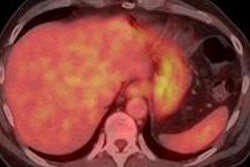

PET/MRI revealed glial activation through C-11 PBR28 binding and significantly higher levels of the translocator protein in the thalamus and other brain regions in patients with chronic lower back pain versus the control subjects.

Images created by averaging PET scan data from chronic pain patients (left) and healthy controls (right) reveal higher levels of inflammation-associated translocator protein (orange/red) in the thalamus and other brain regions of chronic pain patients. Images courtesy of Marco Loggia, PhD.The distinction was so consistent across the subjects that the researchers could differentiate between the two groups simply by looking at the individual images, before a statistical analysis was performed.